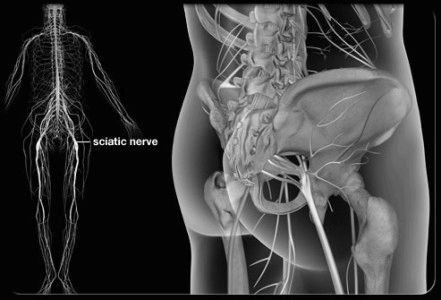

трохи анатомії

Сідничний нерв являє собою найбільший нерв в організмі людини. Беручи свій початок від крижового нервового сплетення, він спускається від сідниць по задній поверхні ніг приблизно до рівня гомілки, де розпадається на дві більш дрібні гілки. Запалення сідничного нерва, яке в медицині отримало назву ішіас, супроводжується характерними болями по ходу нерва. Невралгія сідничного нерва, ішіас не є окремим захворюванням. Це симптомокомплекс, який супроводжує багато патологій хребта.